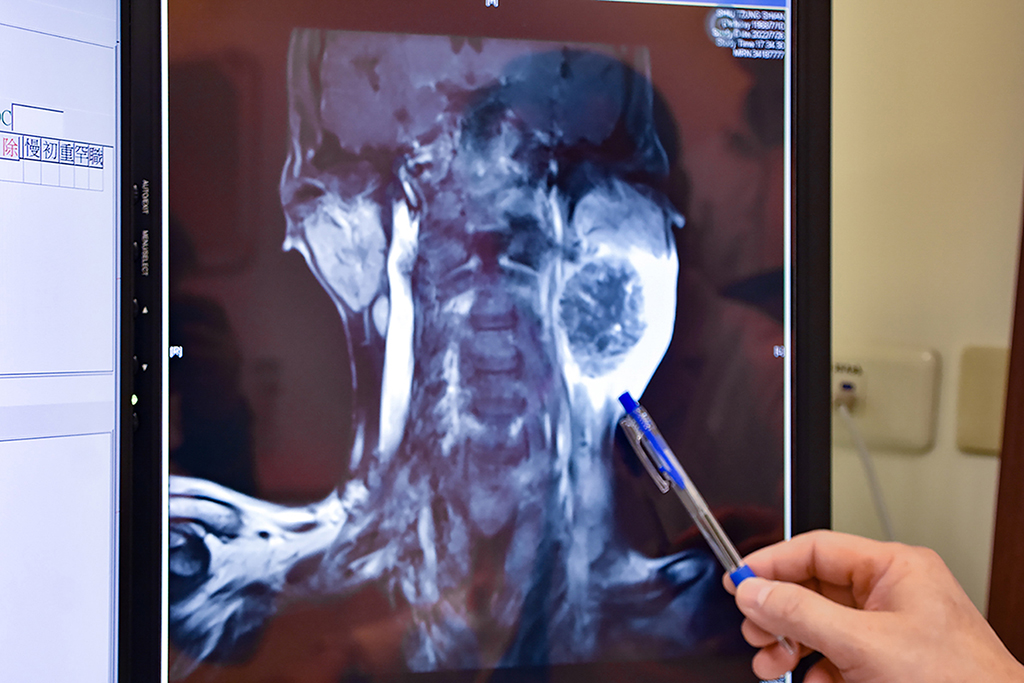

55歲男子因喉嚨疼痛、吞嚥困難、口腔有惡臭味,確診為扁桃腺癌合併嚴重的頸部淋巴擴散;核磁共振顯示嚴重腫瘤侵犯。

同時期,也發生在嘉義一位55歲的男性身上,今年五月開始喉嚨疼痛、吞嚥困難、口腔有惡臭味,但也因害怕疫情的關係不敢就診,以致後續頸部摸到硬塊且逐漸長大到6公分,但也因為都戴著口罩,家人都不知他身體上的變化,直到今年八月疫情趨緩,才終於到醫院尋求治療,這時發現已經是癌症第四期,同時合併有嚴重的頸部淋巴結轉移。在嘉義經大型醫院化療無效,趕緊慕名到彰基醫學中心尋求陳穆寬院長手術治療,彰基頭頸癌團隊迅速為他安排手術,切除半邊鼻咽、口咽及舌底淋巴廓清,並進行顯微重建手術,避免腫瘤持續的長大造成不可挽回的後果。

彰基醫學中心院長陳穆寬教授指出,55歲男子已是癌症第四期,同時合併有嚴重的頸部淋巴結轉移。